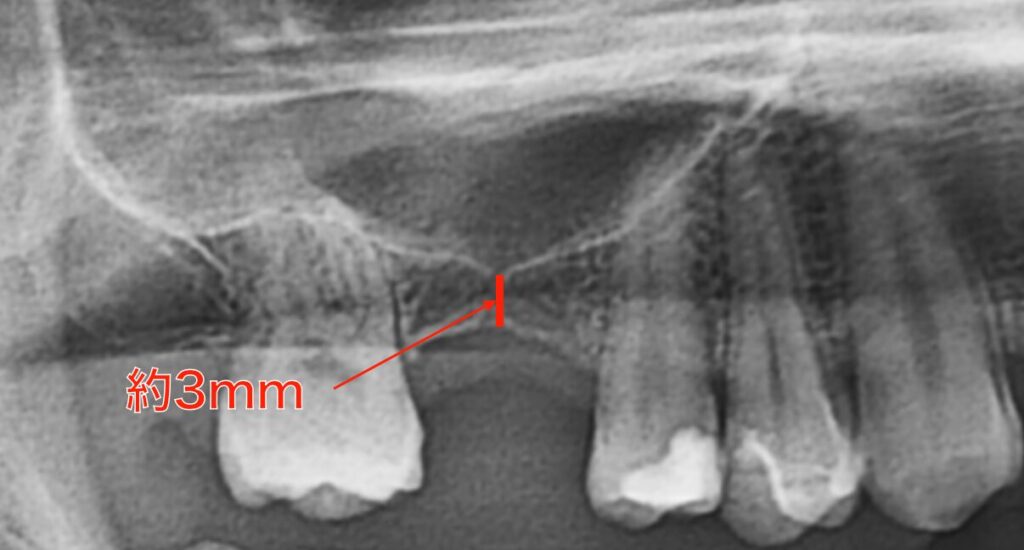

右上奥歯の欠損に対してインプラントを計画しました。

骨量は垂直的に約3mmとかなり薄くなっています。

本来であれば人工骨を移植してのソケットリフトが適応になる症例ですが、今回はグラフトレスでのソケットリフトを計画しました。